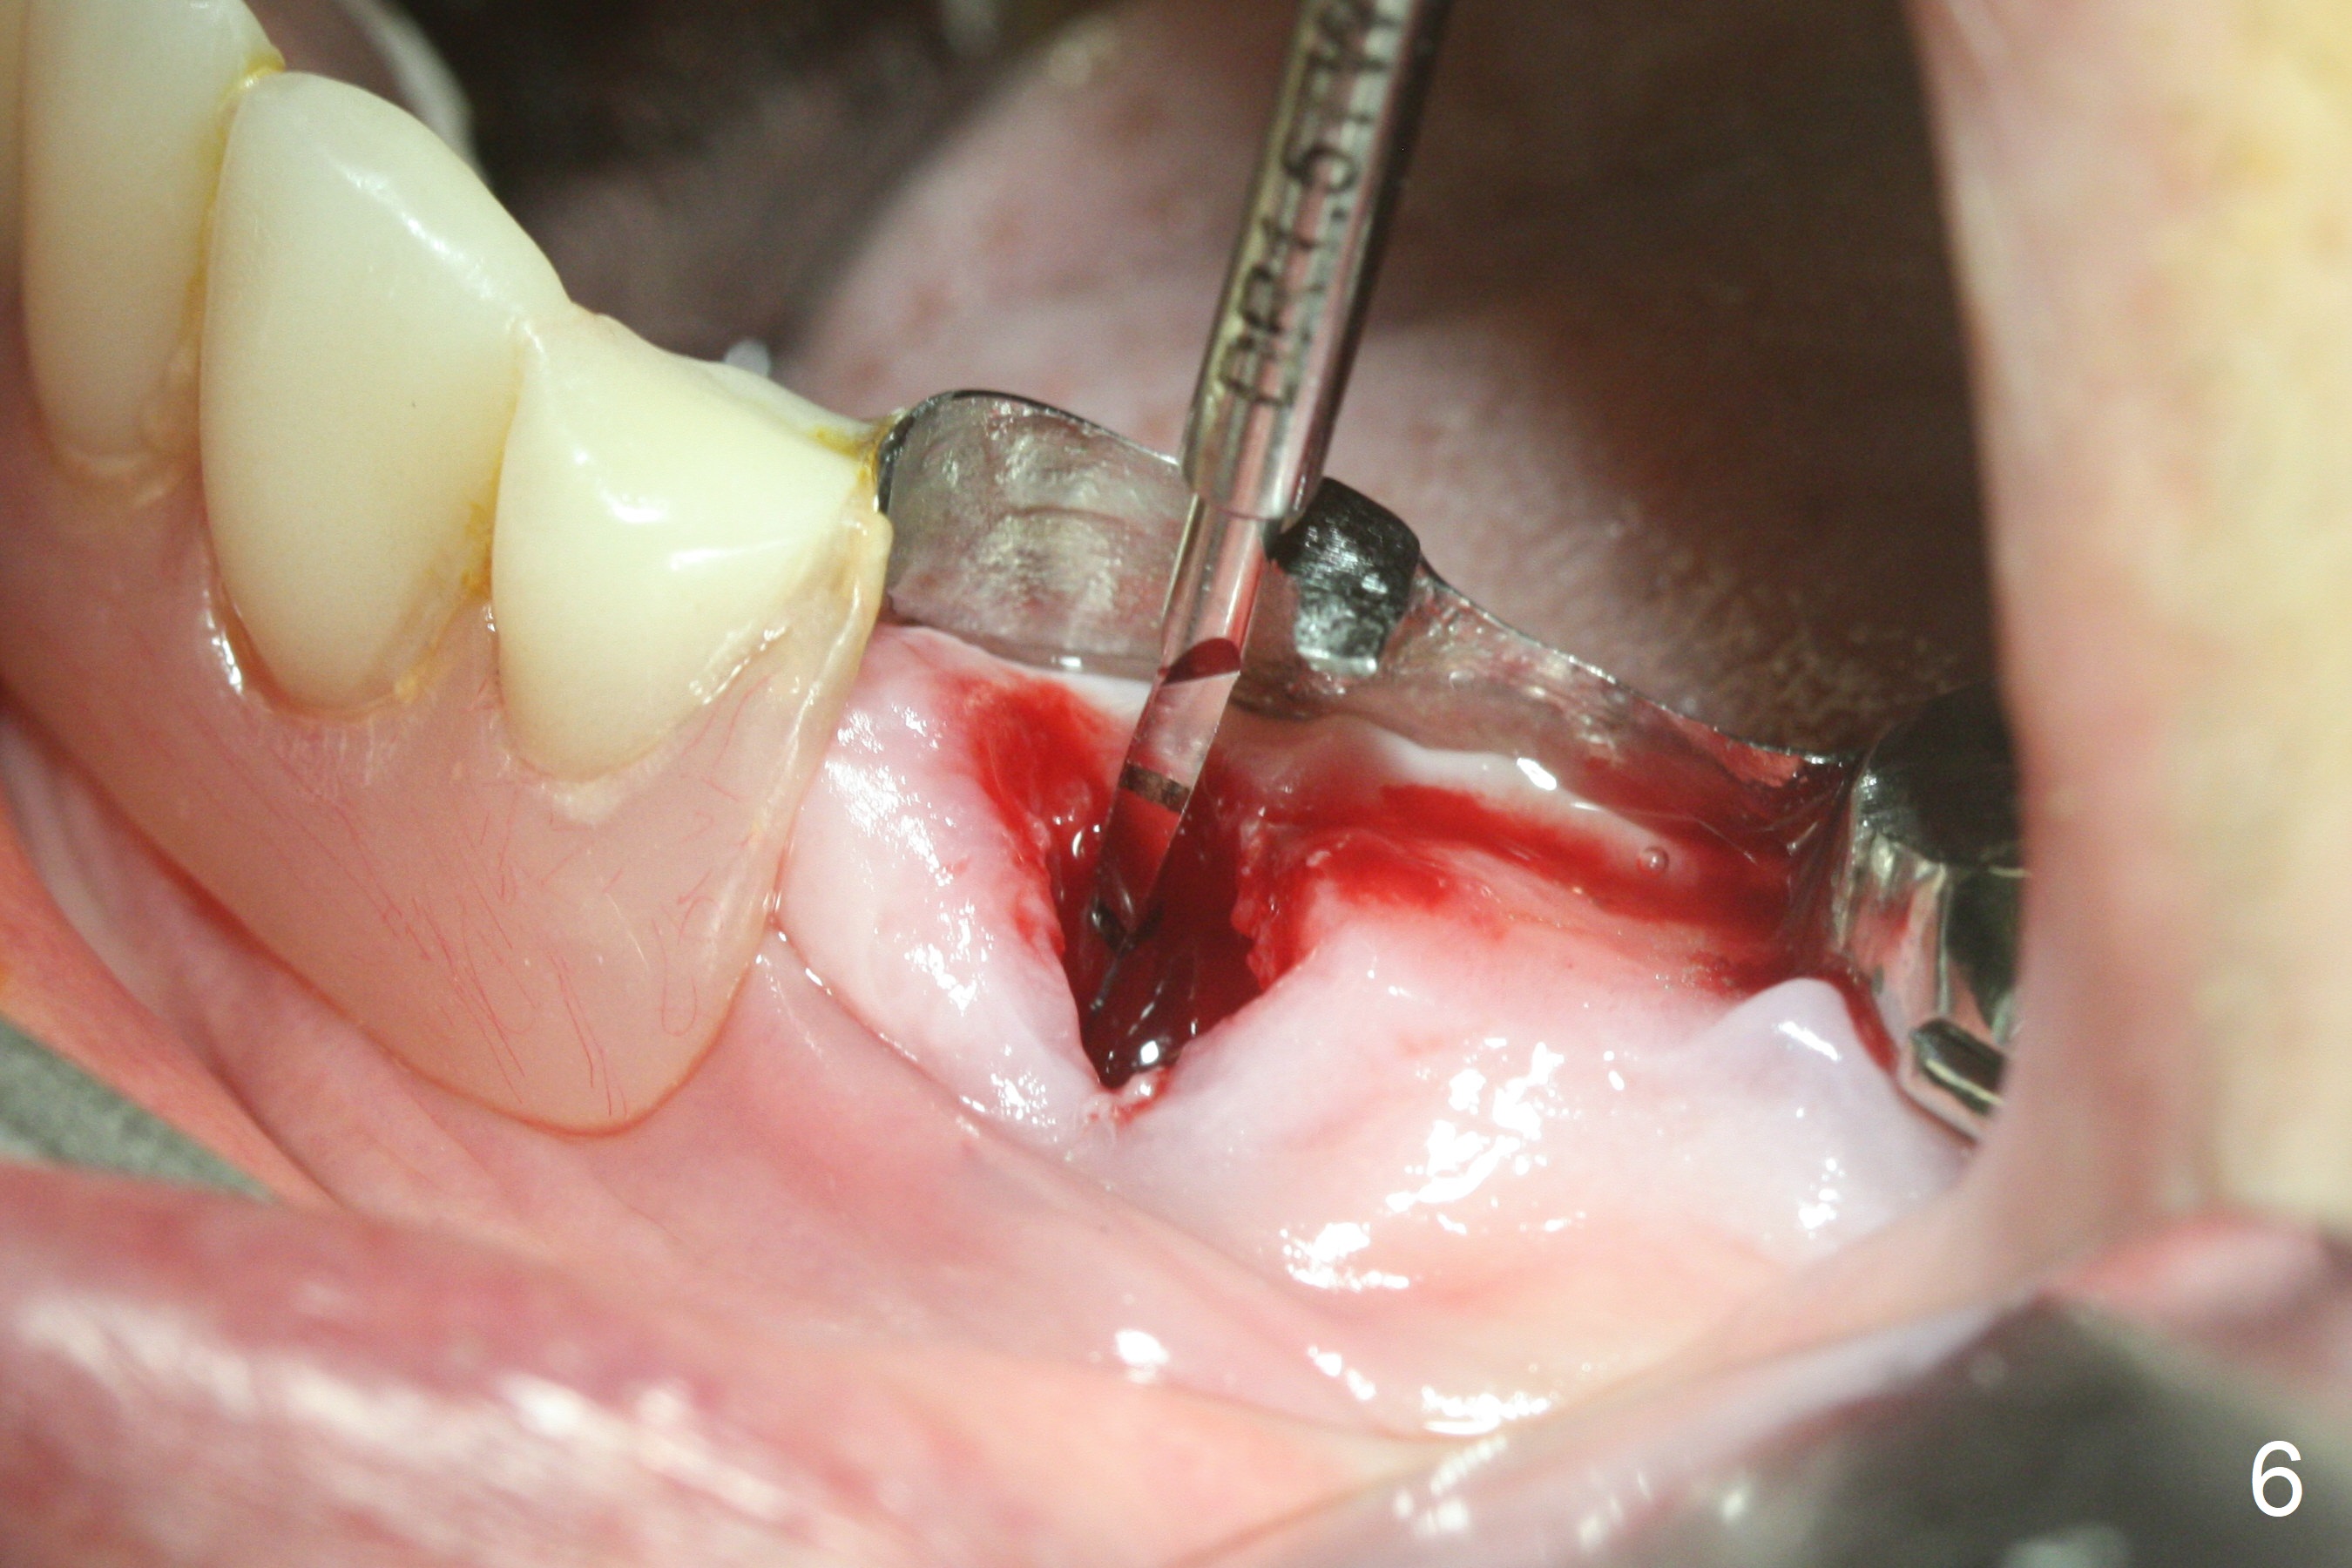

After removal of the pontic at #19 and retainer at #20 (Fig.1) and of vertically fractured root, the buccal plate is found to be defective (Fig.2 *). An implant will be placed as lingual as possible. Since the apex of the affected tooth is coronal to the Mental Loop (Fig.3 red dashed line), an osteotomy (Fig.4 yellow arrow) to be established in the mesial slope (blue dashed line) after extraction (black area) appears to be safer than that along the long axis of the tooth. The initial osteotomy is accomplished by free hand (Fig.5), but when the lower RPD is inserted, the superior end of the 1.5 mm pilot drill is distal (Fig.6). When the trajectory is corrected using the RPD as a surgical guide at the same depth (17 mm gingival level), brisk hemorrhage is from the osteotomy without severe pain. After hemostasis is achieved by packing the socket with Osteogen plug and bone graft and packing bone graft into the osteotomy, 3.3 mm Magic Drill is used for 14 mm. A 4x11 mm IBS implant is placed with 60 Ncm (Fig.7). The implant is then placed deeper, followed by placement of a 4.5x4(3) mm abutment and further bone graft (Fig.8). Finally the implant/abutment complex is apparently in an acceptable mesiodistal position with a large buccal gap which has been filled by bone graft (Fig.9 *). In fact the Mental Loop seems to have been not violated in the procedure (Fig.10). X-ray is taken 3 and 6 months postop. Bone graft (Fig.11,12 (CBCT) *) appears to remain over the buccal (B) surface of the implant coronally 13 months postop (7 months post cementation). The gingiva at #19 and 20 is apparently healthy 8 months post cementation except mild recession at #20 (Fig.13).